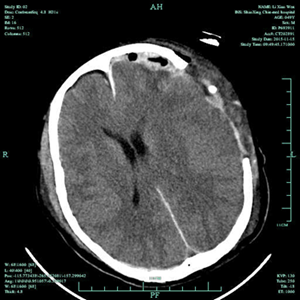

术后2月,患者再次入院,在家属的殷切期望下,我院神经外科积极完善术前准备,排除手术禁忌,于2016年1月14日,在全麻下为患者施行了“颅骨缺损修补术”,置入由计算机预先定制的个体化三维钛网,手术顺利。在十二病区医护的精心照护下,患者恢复顺利,基本恢复了原来的面貌,满意出院。

修补术前 修补术后